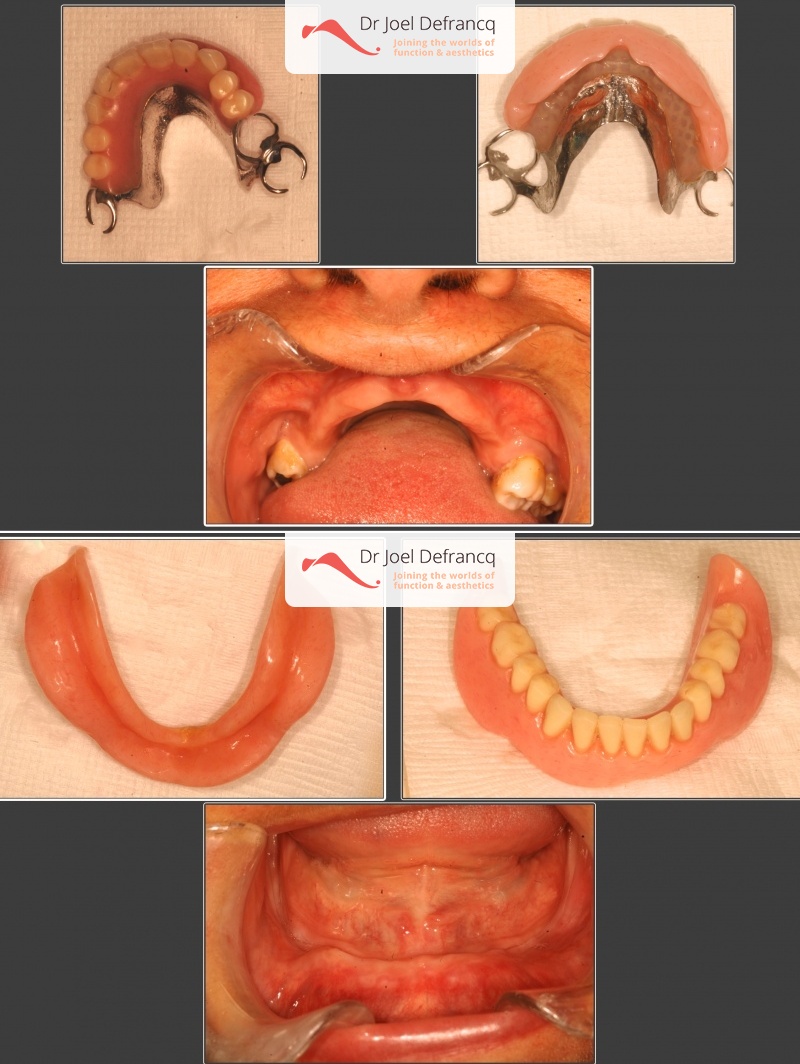

Daphne: from extreme atrophic to fixed teeth on implants

Behandeling tandheelkundige implantaten

- Vaste tanden op implantaten (bovenkaak)

- Vaste tanden op implantaten (onderkaak)

- Implantaten met beenopbouw